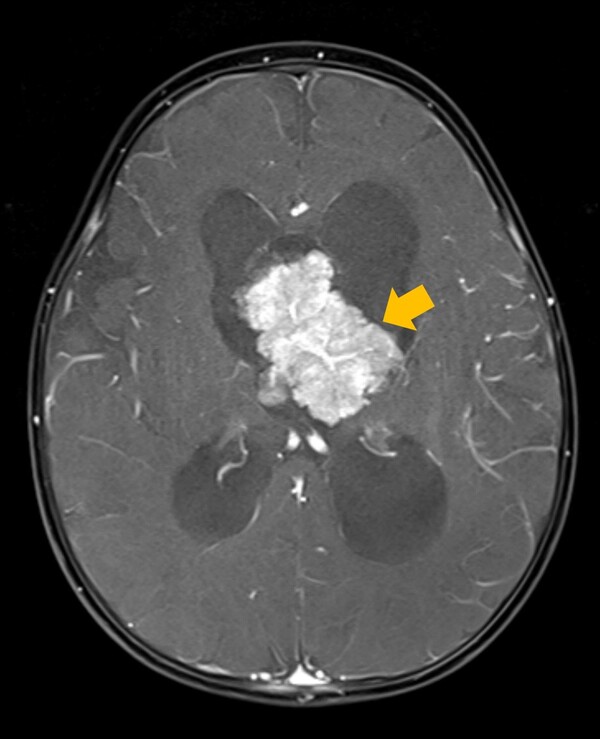

맥락얼기(뇌실 속에 위치한 혈관과 세포로 이뤄진 그물 같은 구조물로 뇌와 척수에서 뇌척수액을 생성함)에서 발생하는 뇌종양인 맥락얼기종양은 양성종양인 '맥락얼기유두종'과 악성종양인 '맥락얼기암종'으로 나뉘는데, 국내 연구진이 이제껏 드러나지 않았던 소아 맥락얼기종양에서의 양성과 악성 종양의 유전적 특성을 규명해냈다.

맥락얼기종양은 전체 소아 뇌종양 환자의 2~6%를 차지하며, 주로 5세 미만의 소아에서 진단된다. 조직학적 특성에 따라 ▲맥락얼기유두종(수술적 제거 후 좋은 예후) ▲비정형 맥락얼기유두종(중간 정도의 예후) ▲맥락얼기암종(빠른 진행과 재발 가능성 높음)으로 분류된다.